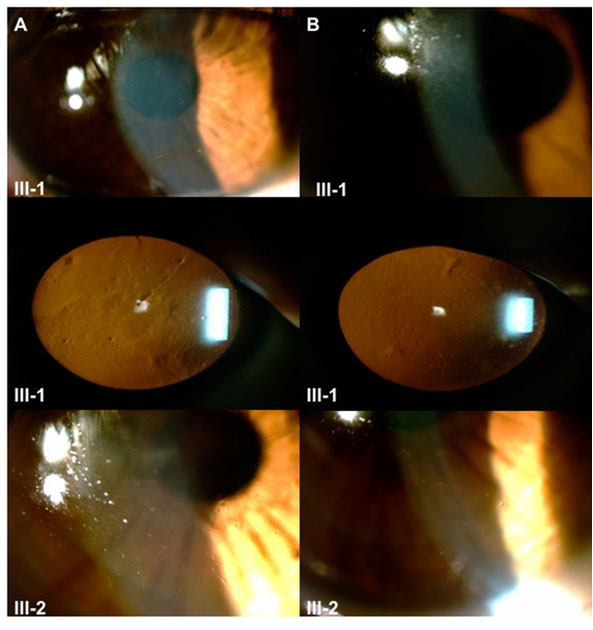

Figure 4. Slit-lamp photographs of subjects III-1 and III-2. Incipient corneal changes corresponding to lattice lines are observed predominantly in the right eye of both subjects. A: Right eye. B: Left eye.